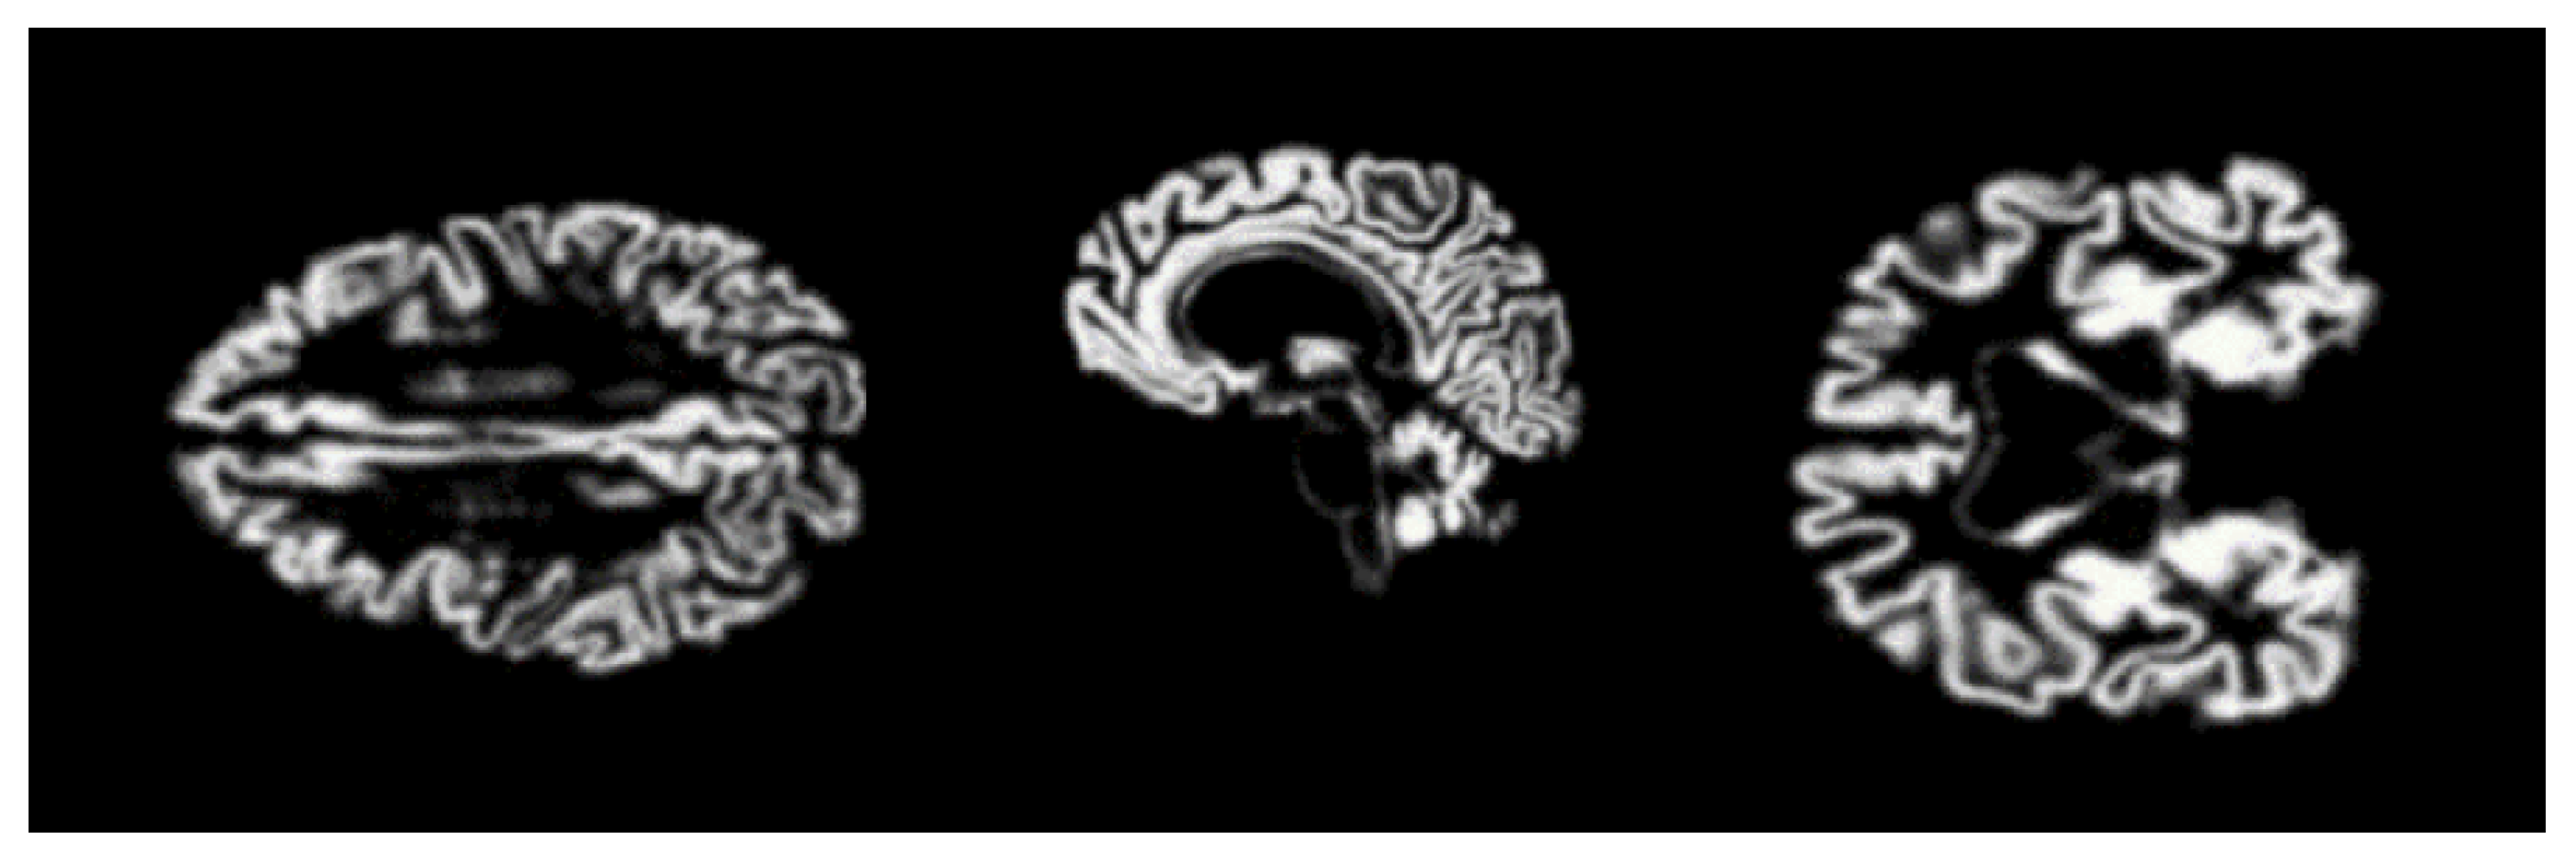

4.2.5. Smoothing

4.2.6. Augmentation